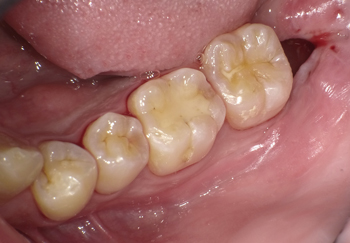

抜歯から2週間後の状態です。痛みや腫れはほとんど無くなり、薬も飲まなくて大丈夫になったそうです。